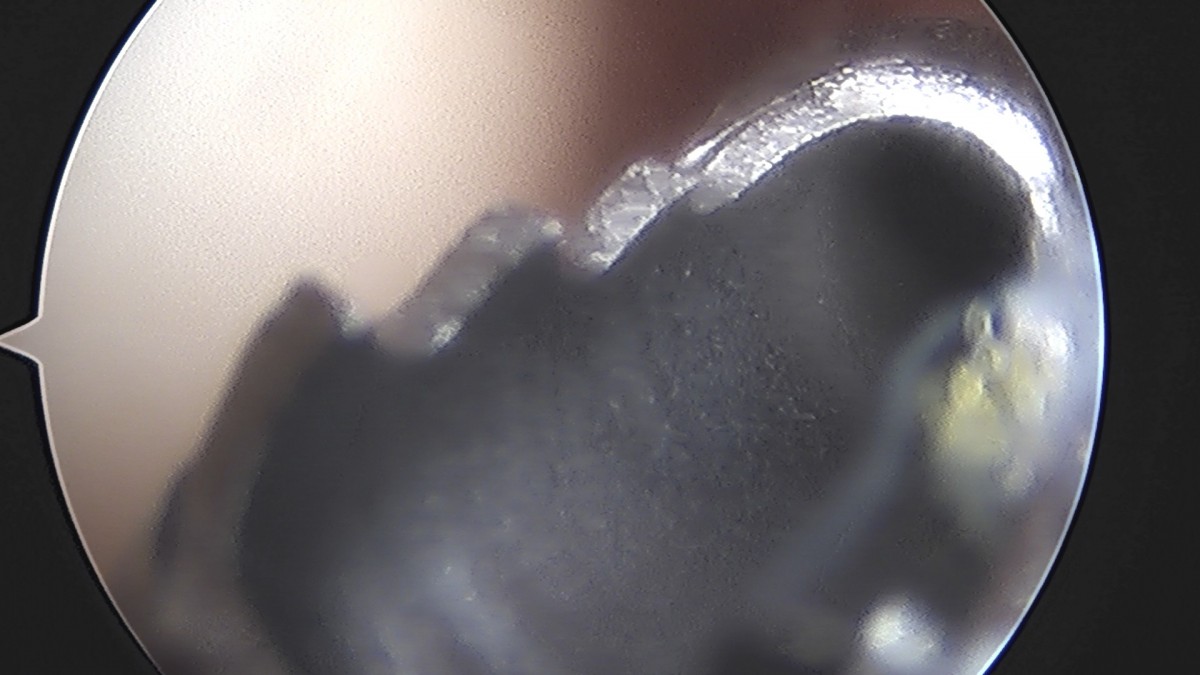

정지영원장님 어깨 관절낭 이완술 및 석회제거술 박설O 환자

작성자 최고관리자 댓글 0건 조회 732회 작성일 25-09-16 16:59